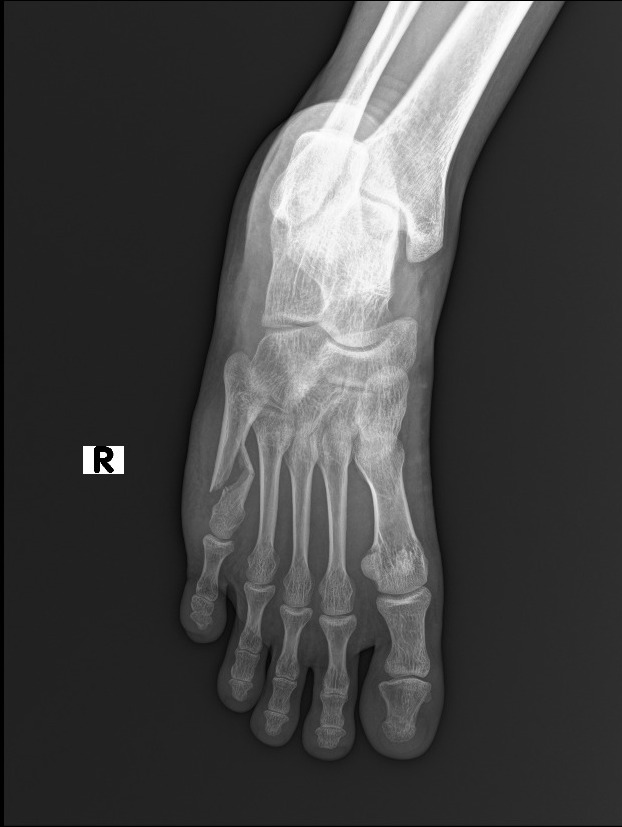

Mau liat rontgennya?

Patah tulang. Bagian metatarsal.

Diapain?

Operasi jam 10 malam, dipasang pen.